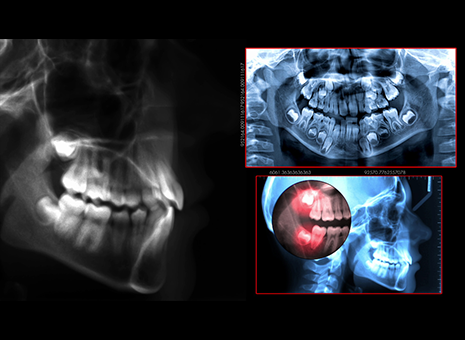

レントゲン

より詳しい歯の状態を知るためにレントゲン撮影を行います。当院で使用しているレントゲンは、従来のものに比べ放射線の量を約1/10〜1/4に抑えています。体に優しいだけでなく、撮った画像も鮮明なので、詳細なデータを基にした治療が行えます。